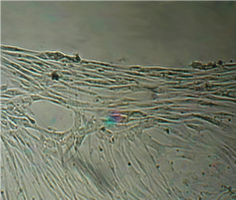

6 серия экспериментов. Образец исследуемого материала (аллогенный ГАП серии «Лиопласт»® массой 2 мг) помещали на дно культуральной чашки, после чего высевали фибробласты в стандартной концентрации.

Щелочной материал резко ухудшает прикрепление фибробластов к дну культуральных чашек (рис. 35) на всей его площади, вместе с тем прикрепившиеся клетки имеют четкие границы, нуклеолемма четко контурирует, цитоплазма гомогенная, без патологической зерностости, вакуолей и включений.

Рис. 35. Выраженная пролиферация, восстановление плотности монослоя.

В последующие дни и до конца наблюдения плотность монослоя  в отдаленной от образца зоне нарастает даже несколько быстрее, чем в контроле, клетки сохраняют обычную для фибробластов в культуре морфологию.

С 3-х суток, когда рН среды во флаконе выравнивалась, начиналось быстрое зарастание дна флакона. К 4 суткам монослой полностью восстанавливался.